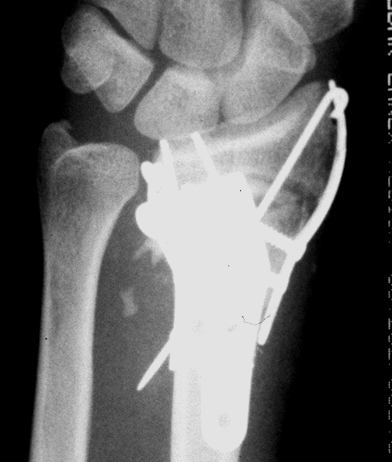

Case 1 Injury

Case 1 Postop